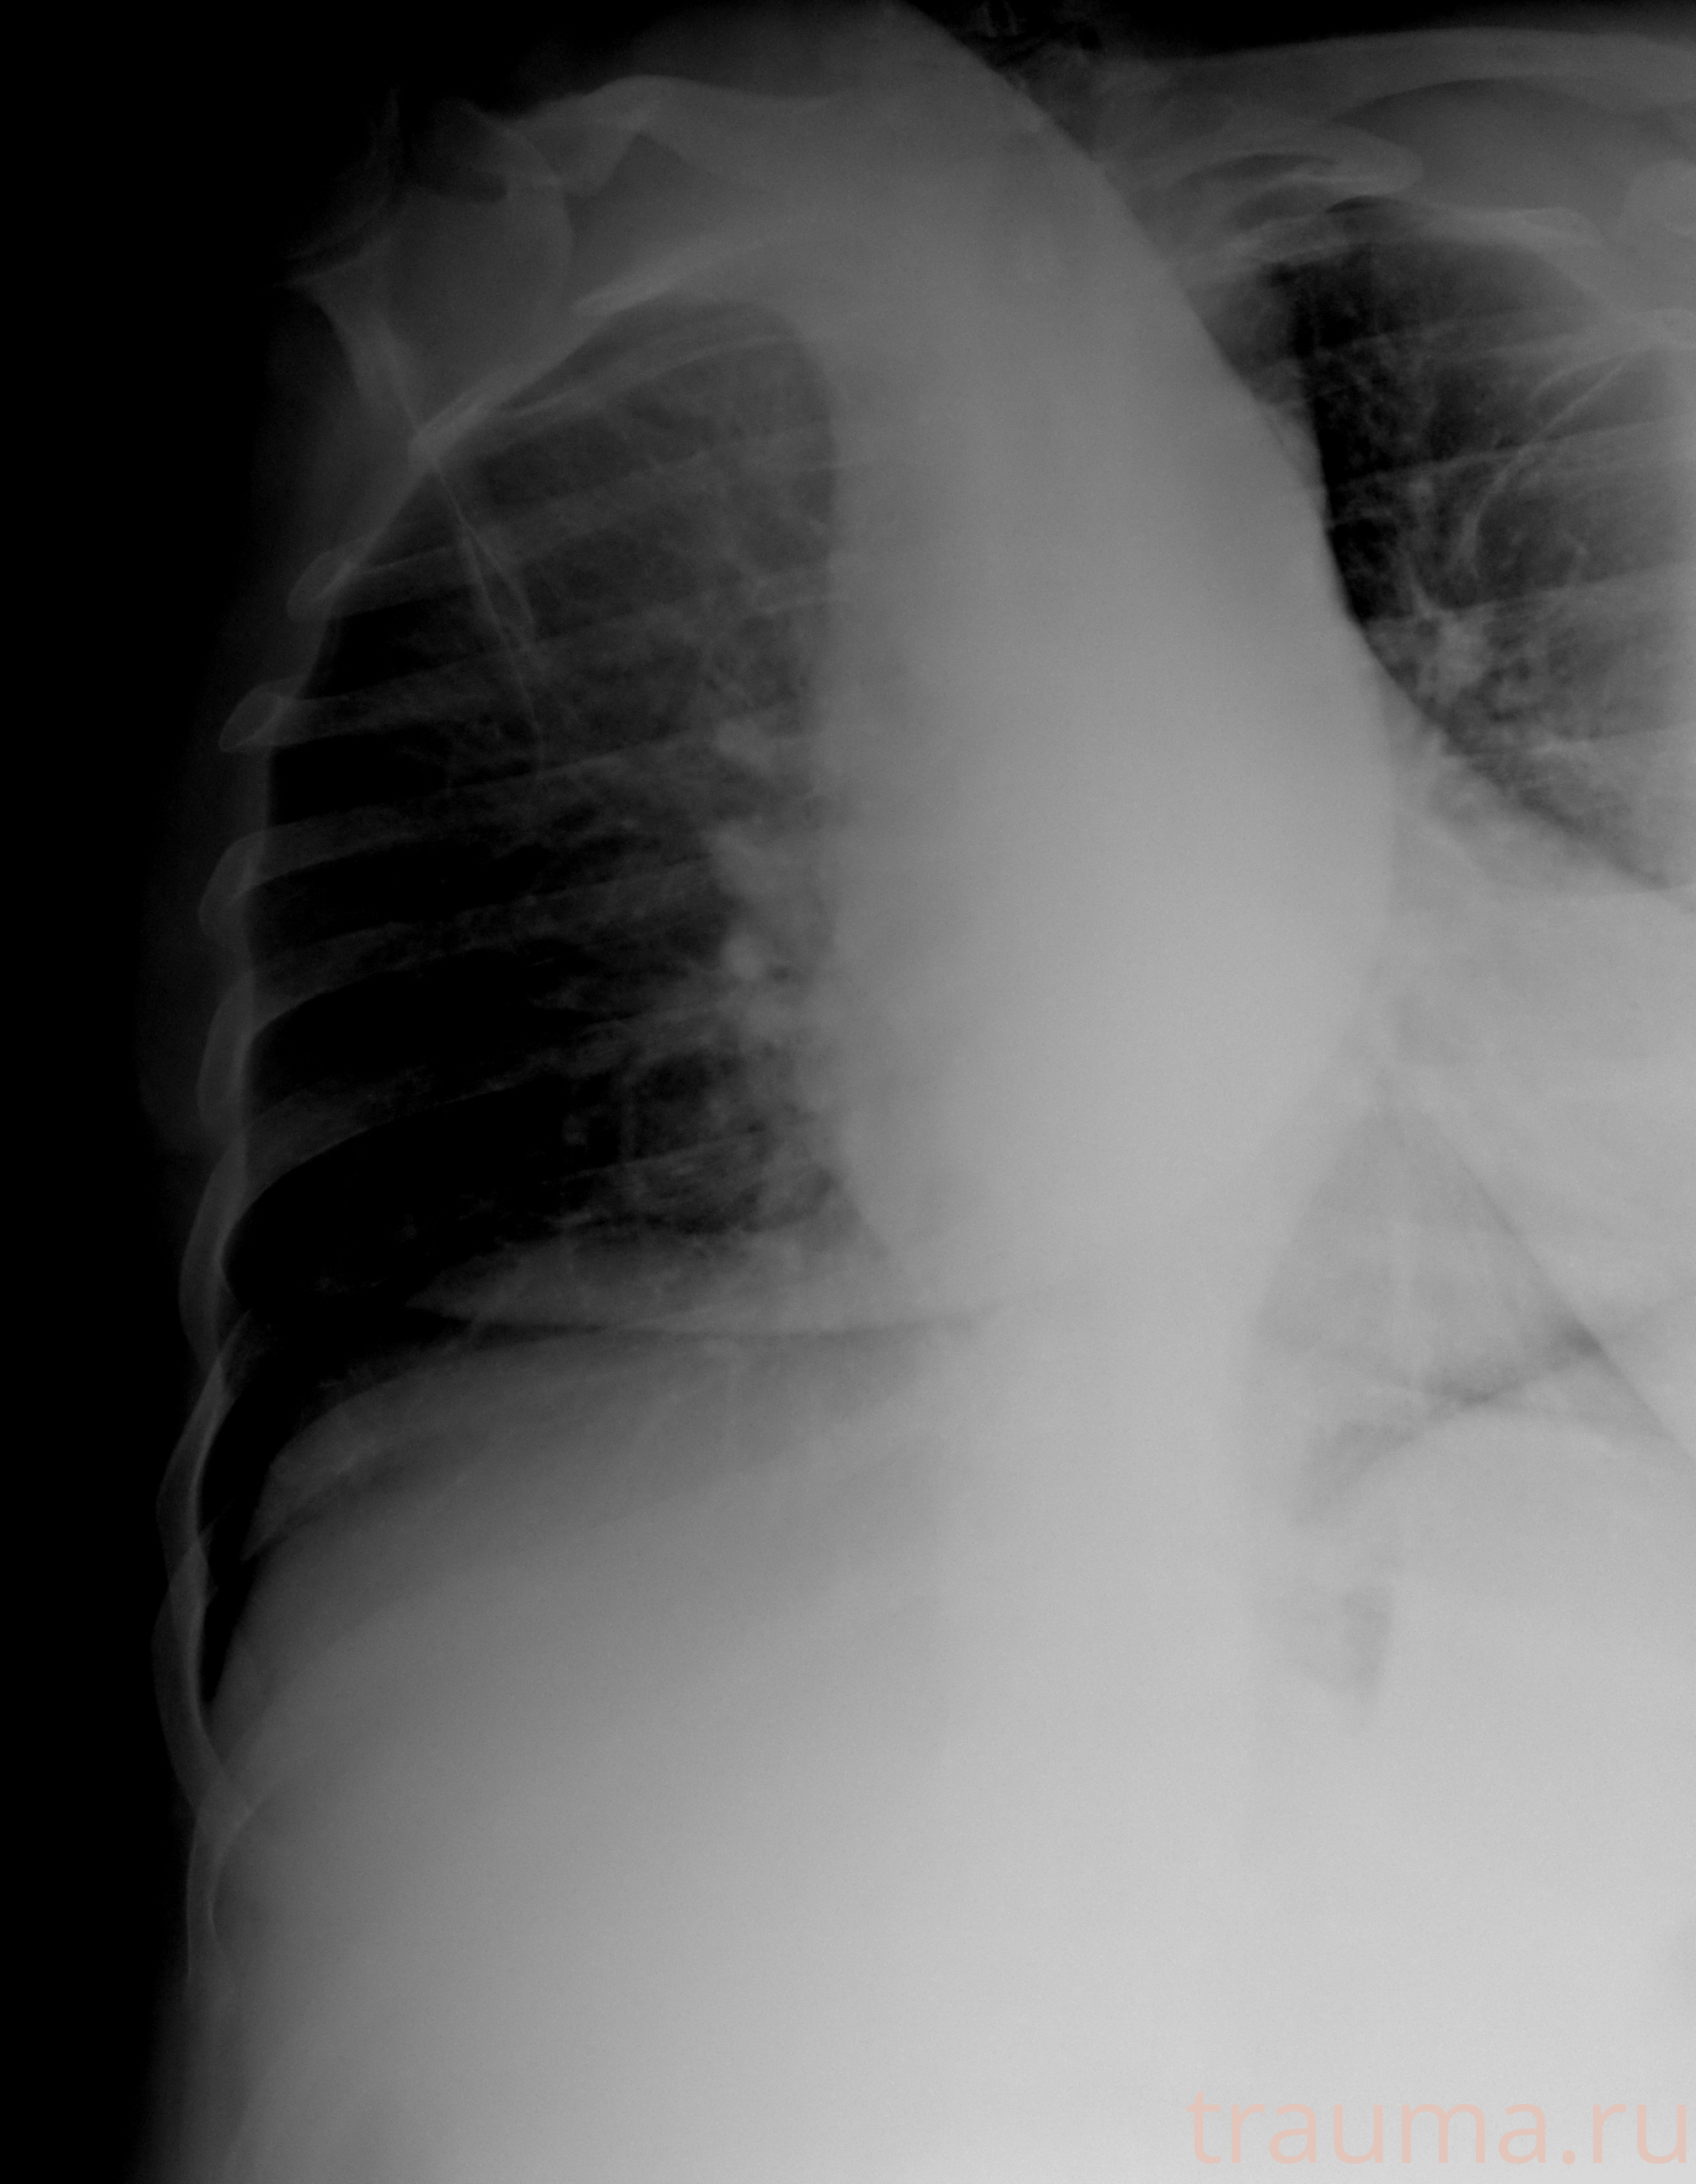

Рентген на дому: по вашему адресу приезжает врач-рентгенолог, травматолог-ортопед с мобильным рентгеновским аппаратом, проводит диагностику травмы или заболевания, делает необходимые рентгенограммы, дает рекомендации по дальнейшему лечению. Получить качественные снимки в домашних условиях возможно благодаря уникальной методике, разработанной МосРентген Центром для института  Склифосовского